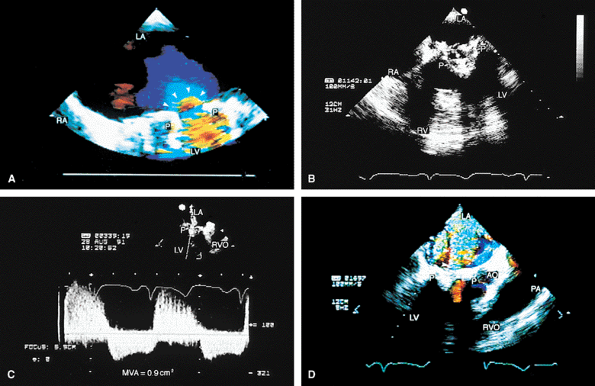

FIGURE 5.19. Porcine mitral prosthesis: stenosis and regurgitation. A. A large diastolic flow acceleration (arrowheads) on the atrial side of the prosthesis (P), suggesting the presence of obstruction. B. Thickening and calcification of the prosthesis resulting from degeneration. C. A decreased slope of the diastolic velocity profile with a measured mitral valve area (MVA) of 0.9 cm2 measured by the pressure half-time technique, indicating significant obstruction. D. Associated severe valvular mitral regurgitation (MR) (arrowheads). Images B through D are from the same patient. AO, aorta; LA, left atrium; LV, left ventricle; PA, pulmonary artery; RA, right atrium; RV, right ventricle; RVO, right ventricular outflow tract. |

|

FIGURE 5.20. Porcine mitral prosthesis: spontaneous contrast and thrombus in the left atrium (LA). A. M-mode study shows spontaneous contrast (arrows). B,C. A large thrombus (TH) in the left atrial appendage (LAA). The prosthetic leaflets are only mildly thickened (B). D. Extensive thrombus formation (TH) in the left atrium in another patient with an obstructed porcine mitral prosthesis. AO, aorta; LV, left ventricle; MVP, mitral valve prosthesis; RA, right atrium; RVO, right ventricular outflow tract. (Creproduced with permission from Mahan EF III, Nanda NC. Transesophageal echocardiography. In: Rackley CE, ed. Challenges in Cardiology I. Mt. Kisco, NY: Futura, 1991:85–101. ) |